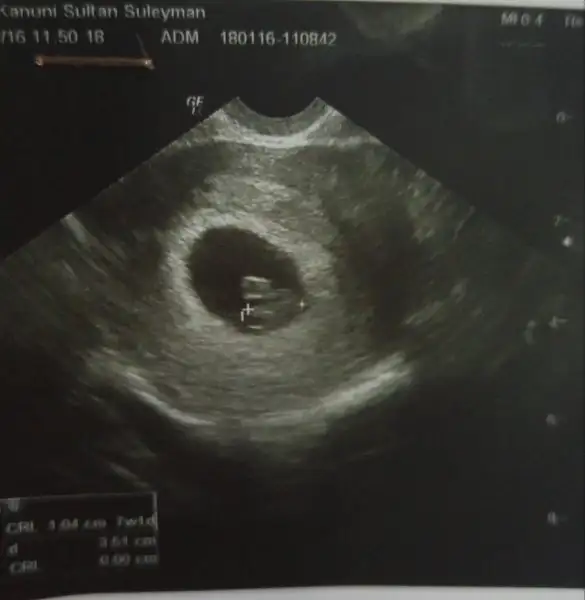

Iste benim mucizem

Eklentiler

• 20160128_141212.webp

20160128_141212.webp

21,3 KB · Görüntüleme: 226